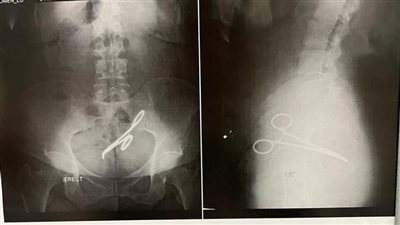

استخراج آلة جراحية ظلت داخل بطن سيدة بالمنصورة 6 سنوات